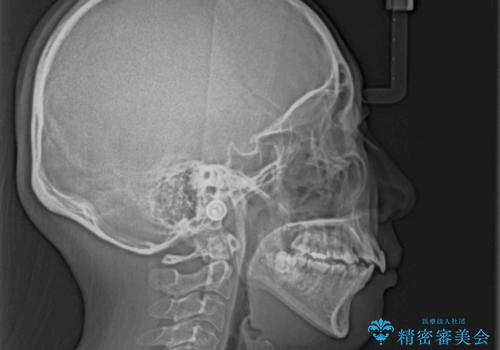

- 八重歯と上下前歯のでこぼこを気にして来院された患者様です。

上下前歯部叢生のスペース獲得のため、上下顎左右小臼歯各1歯(計4本)を抜歯して、ワイヤー装置にて矯正治療を行うこととしました。

上下の正中位置が大きくずれていたため、上下正中が合わないまま終了することが予想されましたが、思っていた以上にスムーズに歯が移動し、満足いただける仕上がりとなりました。